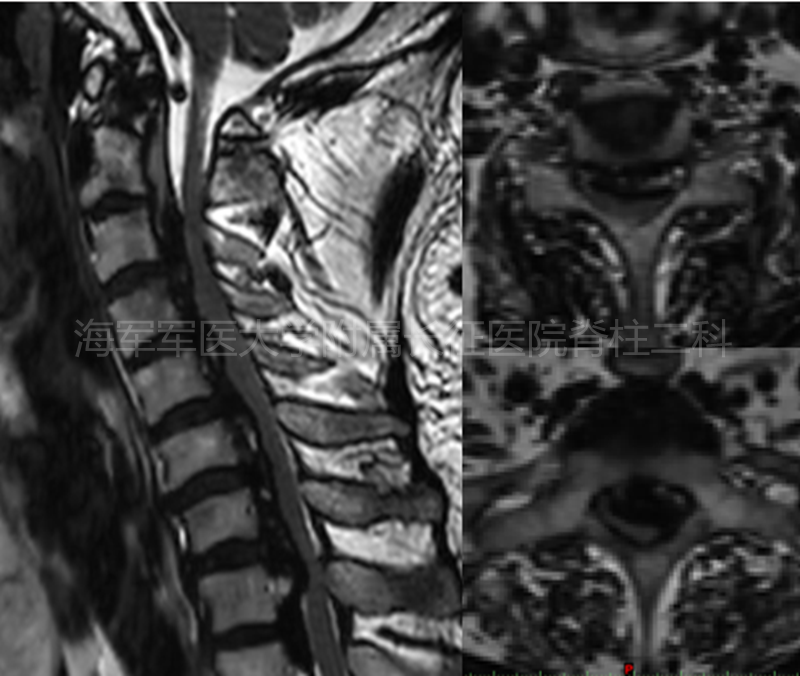

术前矢状位、水平位MRI

术前MRI